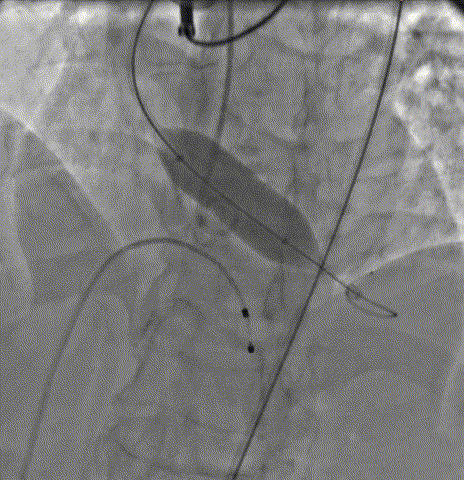

19mm球囊预扩排除冠脉风险